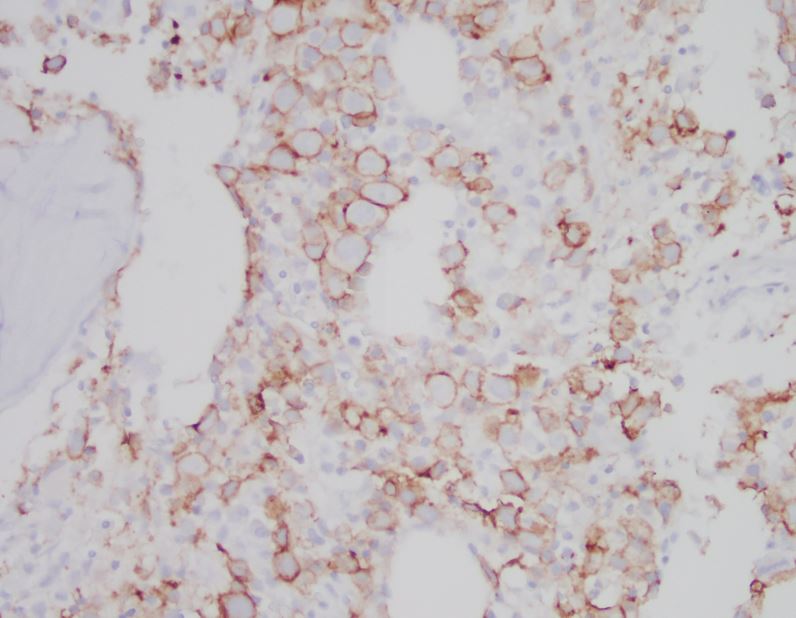

The patient is a 72 year old male with a history of HCC and plasmacytoma. The erythroid lineage is estimated at 82% with 32% pronormoblasts and 1% myeloblasts. E-cadherin and PAS stains are pictured. What is the best diagnosis?

This case meets the criteria for pure erythroid leukemia, a subtype of AML-NOS. In a pure erythroid leukemia, the erythroid lineage must comprise >80% of cells with >30% pronormoblasts. Myeloid blasts must not comprise a significant proportion of the marrow. If myeloblasts are increased to >5%, cases are classified as MDS with excess blasts. If myeloblasts are >20%, cases are classified as AML with myelodysplasia-related changes. Pure erythroid leukemia is a rare entity that is more common in patients with a preexisting MDS or as a therapy-related disease. Morphologically, there is dysplasia in the erythroid lineage cells present, often with PAS-positive cytoplasmic vacuoles, as in this case. The pronormoblasts are positive for CD71, E-cadherin, CD117, and negative for HLA-DR and CD34. Flow cytometry may not be helpful, as the erythroid lineage is lysed prior to analysis.